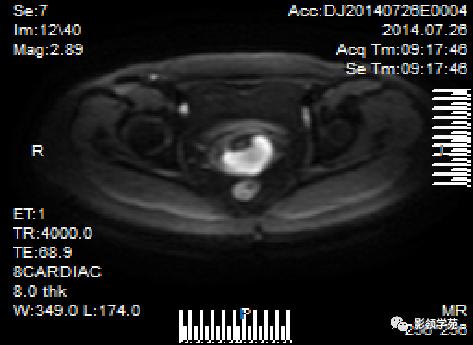

宫颈癌MRI表现

宫颈癌可表现为类圆形或不规则形肿块,在T2WI上表现为均匀或欠均匀的高信号,与正常宫颈基质及宫旁脂肪形成良好的自然对比。

DWI:局限性高信号,癌组织ADC值<癌旁组织<小于正常宫颈组织